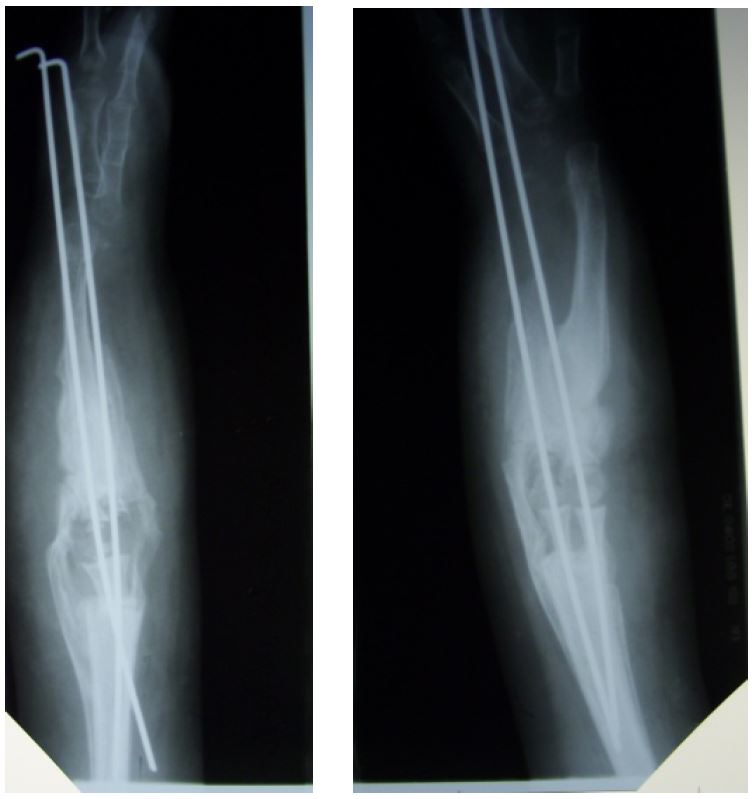

Техника проведения операции: по передней и задней поверхностям правой верхней конечности в проекции синостоза произвели фигурный разрез. После мобилизации мягких тканей и сосудисто-нервных пучков выделена область синостоза лучевой и плечевой костей. Согласно разработанному заводом изготовителем индивидуальному плану, произведены поперечные остеотомии плечевой и лучевой кости. При помощи бура расширен костномозговой канал плечевой и лучевой кости, после чего в канал введен цементирующий материал и внедрены лучевой и плечевой компоненты энодпротеза. После затвердевания материала компоненты эндопротеза скреплены между собой специальным замком. Интраоперационно получено сгибание в локтевом суставе до 110º, разгибание – полное. Правая верхняя конечность иммобилизована гипсовым лонгетом в положении максимального сгибания в локтевом суставе (рис. 3).

Рис. 3. Пациент Б.: а – рентгенограмма верхней конечности до проведения эндопротезирования локтевого сустава; б, в – внешний вид верхней конечности после установки индивидуального эндопротеза локтевого сустава; г, д – рентгенограммы верхней конечности после установки индивидуального эндопротеза локтевого сустава

Течение послеоперационного периода гладкое, с 3-х суток начата пассивная, а с 10-х – активная разработка движений в правом локтевом суставе. Швы сняты на 21-е сутки. На контрольном осмотре через 4 месяца отмечался хороший функциональный результат. Сгибание в правом локтевом суставе до 100º, разгибание полное. По данным рентгенографии правой верхней конечности компоненты эндопротеза стабильны, видны единичные, не блокирующие локтевой сустав оссификаты. Через один и два года амплитуда движений в правом локтевом суставе без изменений. Рентгенологическая картина прежняя. Пациент удовлетворен результатом лечения ввиду появившейся в результате оперативного лечения возможности самообслуживания (рис. 4).

Рис. 4. Пациент Б. через 2 года после установки индивидуального эндопротеза локтевого сустава: а, б – внешний вид верхней конечности; в, г – рентгенограммы верхней конечности